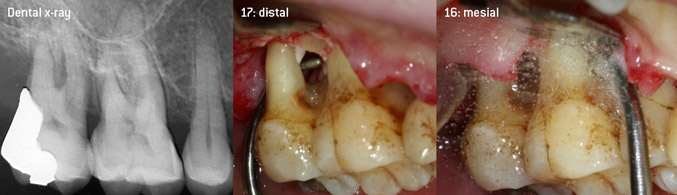

As initiators of the development of the new diamond-coated 3AP air scaler tip, the two dentists recognized the need for improvement of the handling restrictions of the commercially available diamond-coated tips, especially during furcation treatment and when working in tight intraosseous pockets. This should be possible for both non-surgical (Figure 2) and surgical (Figure 3) procedures.

Open debridement of the furcations on teeth 16 and 17

Fig. 3: Open debridement of the furcations on teeth 16 and 17 in case of advanced attachment loss